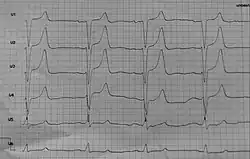

Bei einer Hyperkaliämie fallen im EKG eine spitze hohe T-Welle, der Verlust der P-Welle und eine Verbreiterung des gesamten QRS-Komplexes (insbesondere Rechtsschenkelblock) auf. Die EKG-Veränderungen weisen aber eine nur geringe Sensitivität und Spezifität auf. EKG-Kontrollen ersetzen daher bei der Überwachung einer kaliumsenkenden Therapie nicht regelmäßige Kalium-Kontrollen.[2]